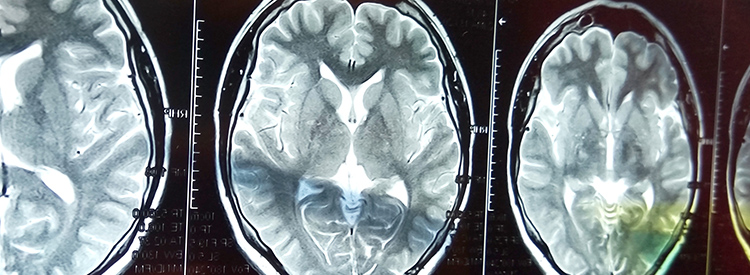

當(dāng)大腦部分血流被切斷時(shí),就會(huì)發(fā)生中風(fēng)。當(dāng)這種情況發(fā)生時(shí),失去血液供應(yīng)的腦組織就會(huì)受傷或死亡。根據(jù)大腦受損區(qū)域控制的功能,這會(huì)導(dǎo)致身體功能喪失。例如,如果控制左臂運(yùn)動(dòng)的區(qū)域受損,該臂就會(huì)變得虛弱或癱瘓。如果左臂控制感覺的區(qū)域也受到影響,手臂會(huì)麻木,或者也可能有燒灼感或疼痛感。由于大腦控制著我們所有的運(yùn)動(dòng)和感覺,包括視覺和言語,因此幾乎任何事物都可能受到中風(fēng)的影響。

中風(fēng)治療進(jìn)展緩慢。如果在最初幾分鐘內(nèi)進(jìn)行治療,可以在急診室或醫(yī)院使用特殊藥物(阿替普酶或組織纖溶酶原激活劑)來逆轉(zhuǎn)或限制缺血性中風(fēng)造成的損害。這種藥物可以分解阻塞血管的凝塊。如果在最初的幾分鐘到幾小時(shí)內(nèi)使用,可以避免或限制對(duì)大腦的任何損害。在使用阿替普酶之前,必須進(jìn)行 CT 成像來確定中風(fēng)類型,以確認(rèn)中風(fēng)不是出血性的。由于阿替普酶會(huì)分解血栓,因此如果用于出血性中風(fēng),可能會(huì)導(dǎo)致嚴(yán)重惡化或死亡。有時(shí)會(huì)治療出血性中風(fēng)以避免進(jìn)一步出血。